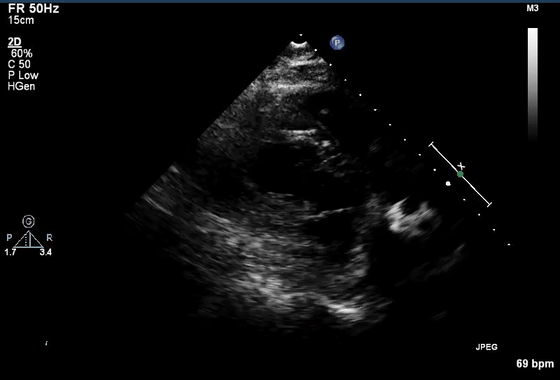

10、经食管超声图像伪像

虽然上面介绍的主要集中在常规经胸超声心动图,但上述伪像也经常在经食管超声心动图中遇到。图10显示了经食管超声心动图中一些常见的伪像。在这方面最相关的临床情况是(1)排除LAA中的血栓(图10E和10F)和(2)排除主动脉夹层(图10G和10H)。

图10经食管图像伪影。

(A)二尖瓣小叶的混响伪影,距离探头正好两倍,表现为左心室腔内的导线(视频15)。

(B)机械主动脉瓣在右心室(RV)(星号)的大部分上投射声学阴影,并在侧面(箭头)投射混响(彗星尾)(视频16)。

(C)房间隔穿刺的导管,由于在(中空)导管上下侧的反射,出现一系列紧密间隔的混响(箭头),并且由于在探头本身的反射,在距离探头两倍的距离处出现一个混响。

(D)疑似两个平行的主动脉(Ao)的镜像伪影(星号)。注意血流也产生镜像伪像(视频17)。

(E)左心耳疑似血栓的混响伪影。从多个角度(见图F)进行分析证实存在华法林嵴的混响(星号),而不是真正的血栓(视频18-19)。

(G)在升主动脉(视频20)中延伸的钙化窦管连接(箭头)的旁瓣伪影(箭头)不应被误解为夹层。

(H)同样,升主动脉中的回声可能会被误解为夹层。